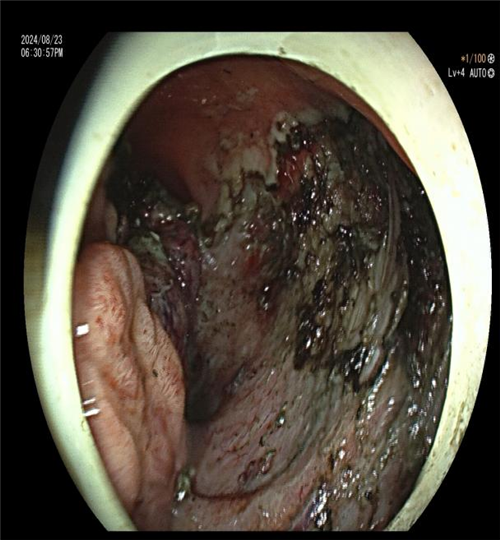

科主任曾春辉在与患者及家属商讨手术方式时,了解到患者极度排斥外科手术,因其病变位置特殊,距离肛门仅 2.5cm,开刀恐难以保住肛门,患者表示宁愿不做手术也不愿生活质量低下。尽管病变巨大且位置特殊,内镜手术难度大、风险高,已超出常规 ESD 手术范畴,但曾主任毅然决定挑战技术极限。他在全麻下为患者施行 “内镜下直肠下段侧向发育息肉 ESD 术(隧道内镜技术)”,手术顺利完成。

相较于肿瘤的外科手术治疗,患者不仅实现了肿瘤完整切除,还成功保留了肛门,生理功能良好,生活质量显著提升。